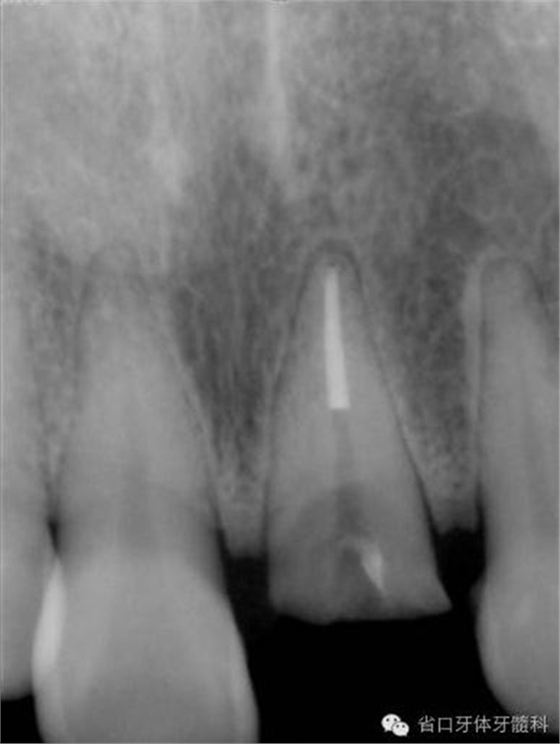

圖8. 21/行根管治療術,保留根尖約5mm的根充物,根中上段預留空間以預備纖維樁道。

圖13. 纖維樁及斷冠粘接固定